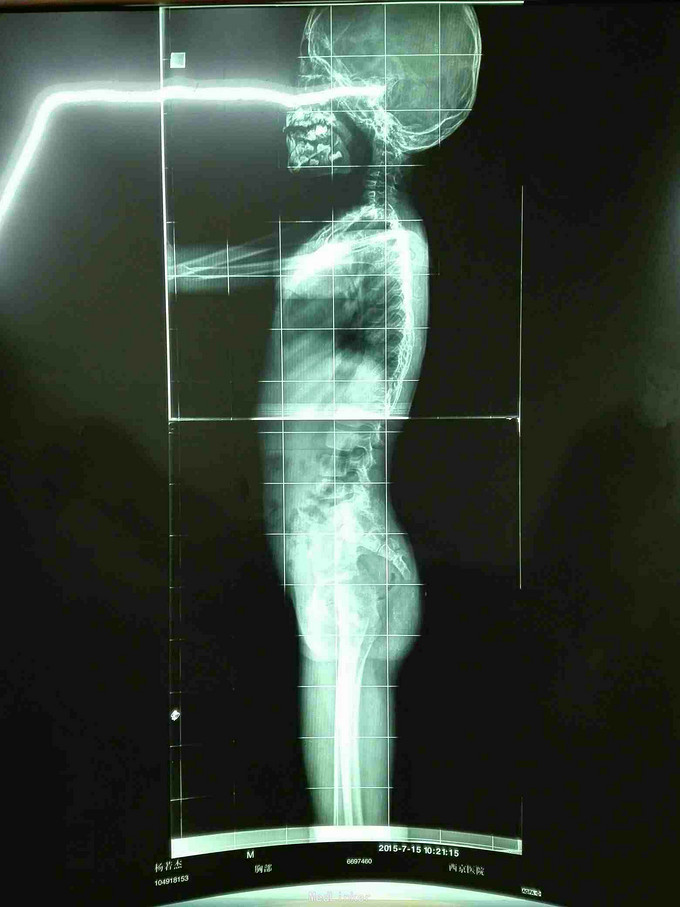

先天脊柱畸形

先天脊柱畸形8年。

严重脊柱畸形病例

先天性脊柱侧凸畸形

脊柱先天畸形